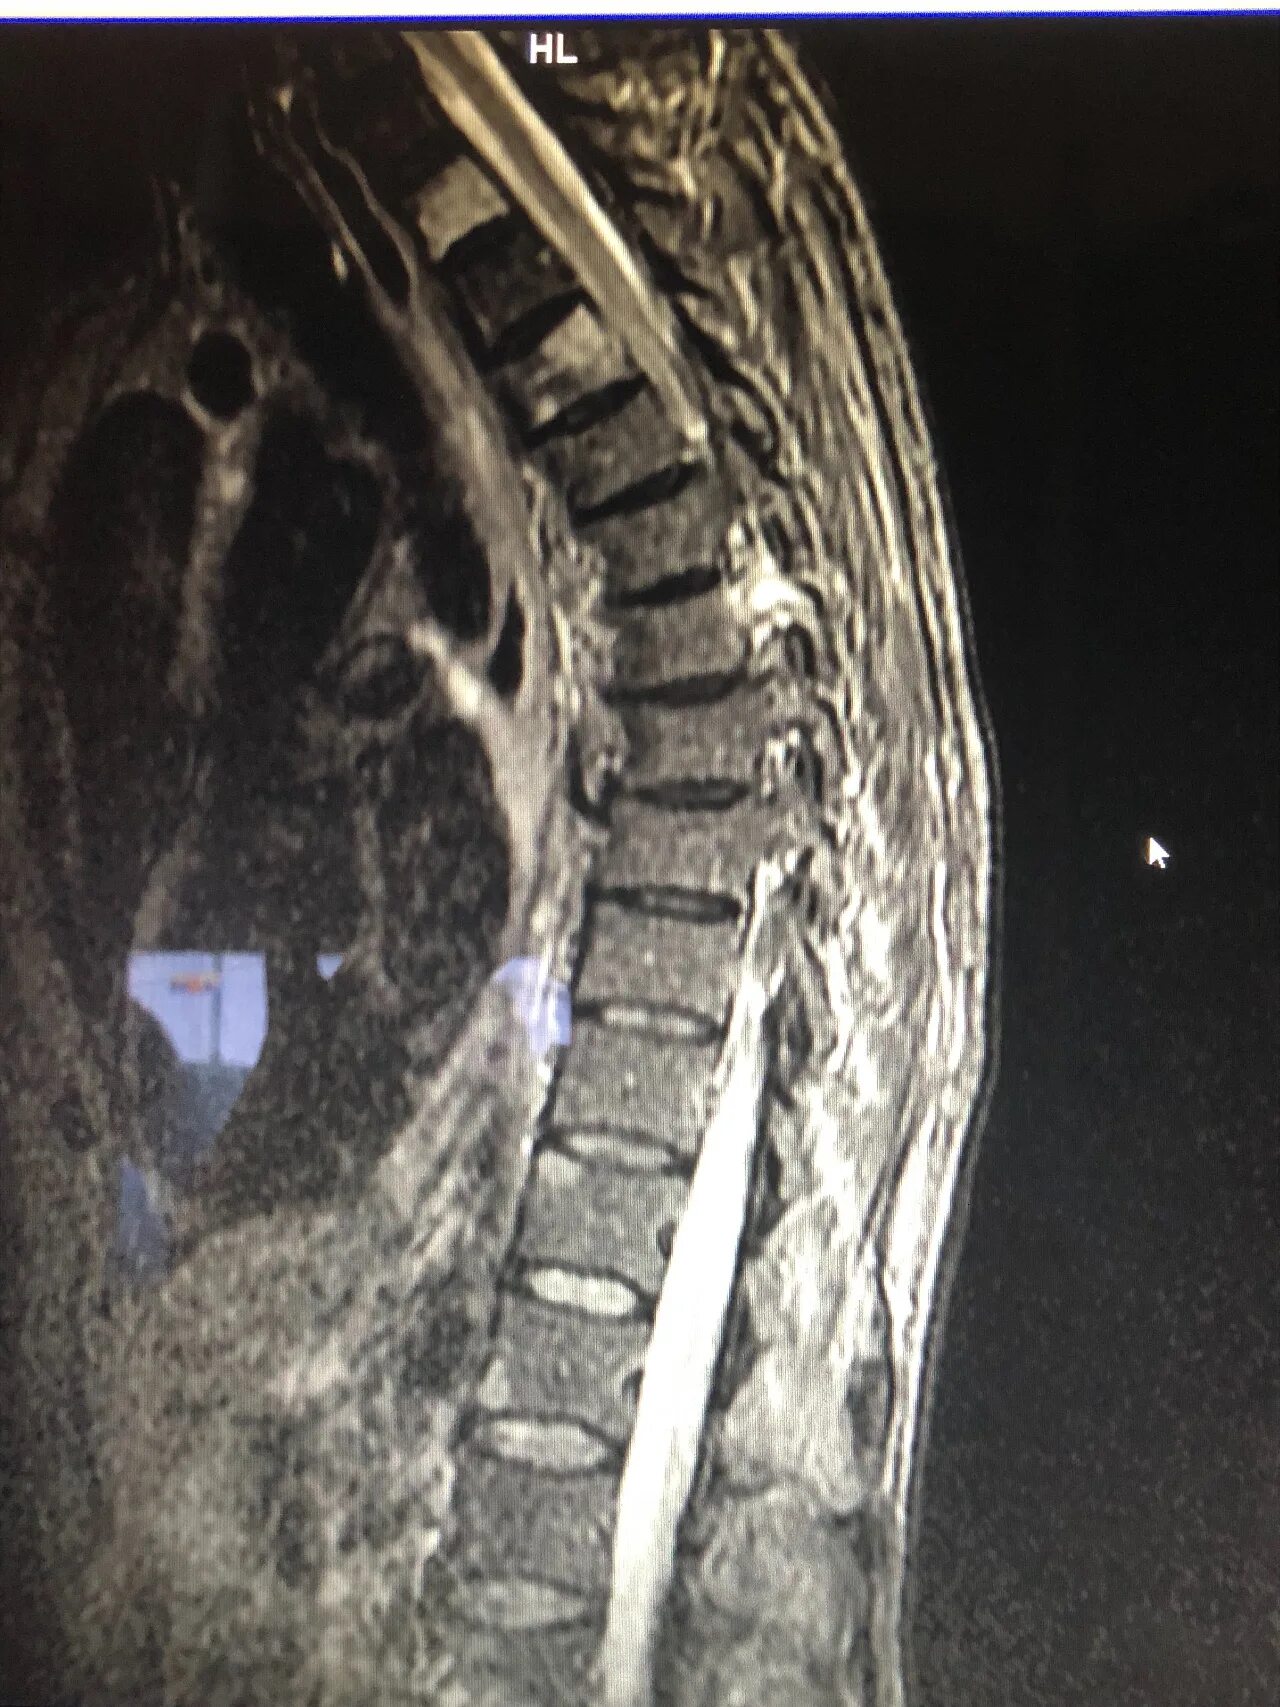

Метастазы костей мрт